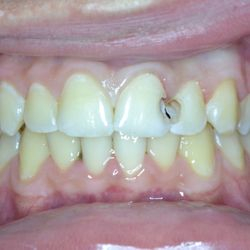

Νεαρός ασθενής 15 ετών προσήλθε στο ιατρείο μας για αποκατάσταση των τερηδονισμένων προσθίων άνω δοντιών του.

Μετά την αφαίρεση της τερηδόνας και την προετοιμασία των δοντιών,έγινε τοποθέτηση σφραγισμάτων σύνθετης ρητίνης τελευταίας γενιάς (HerculiteXRVUltra/Kerr) και αποκαταστάθηκε το χαμόγελο με τον πλέον αισθητικό τρόπο.